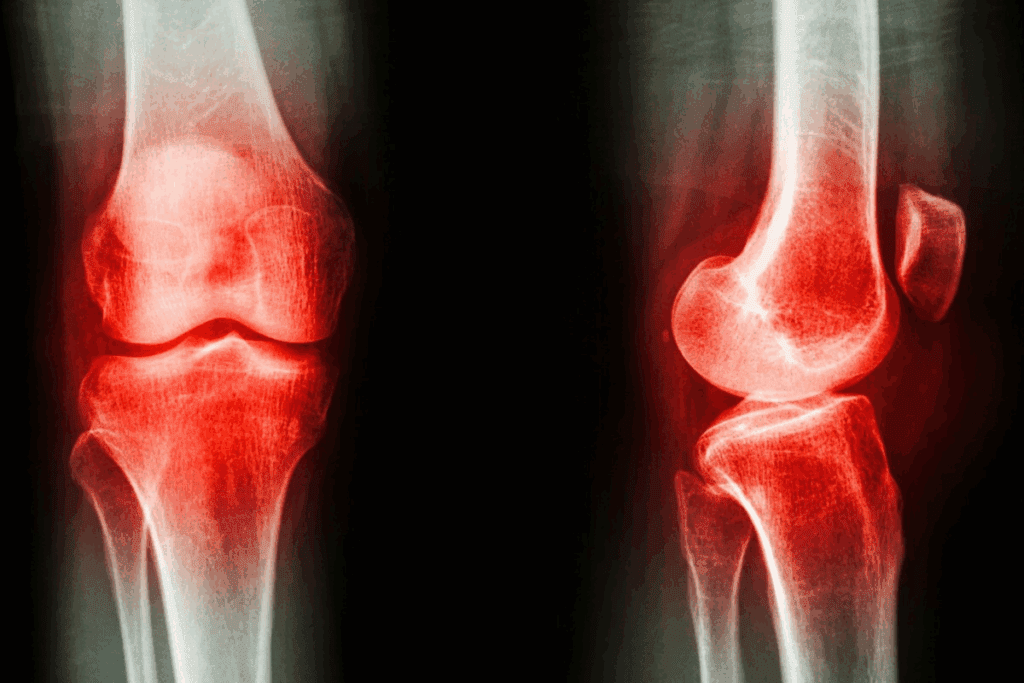

Imaging tests are vital for diagnosing knee pain. X-rays check bone health and look for fractures or wear and tear. Magnetic Resonance Imaging (MRI) shows soft tissue details, like ligaments and cartilage, helping spot injuries or conditions like tendinitis.